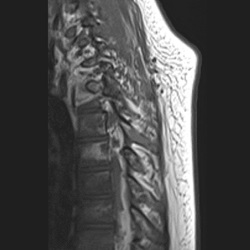

#AJNRcc >> November 11, 2024 >> What is the diagnosis for this 54-year-old woman admitted for paresthesia of the lower limbs with laboratory tests revealing an HIV infection? Submit your answer at https://t.co/6aANs07WZ8.